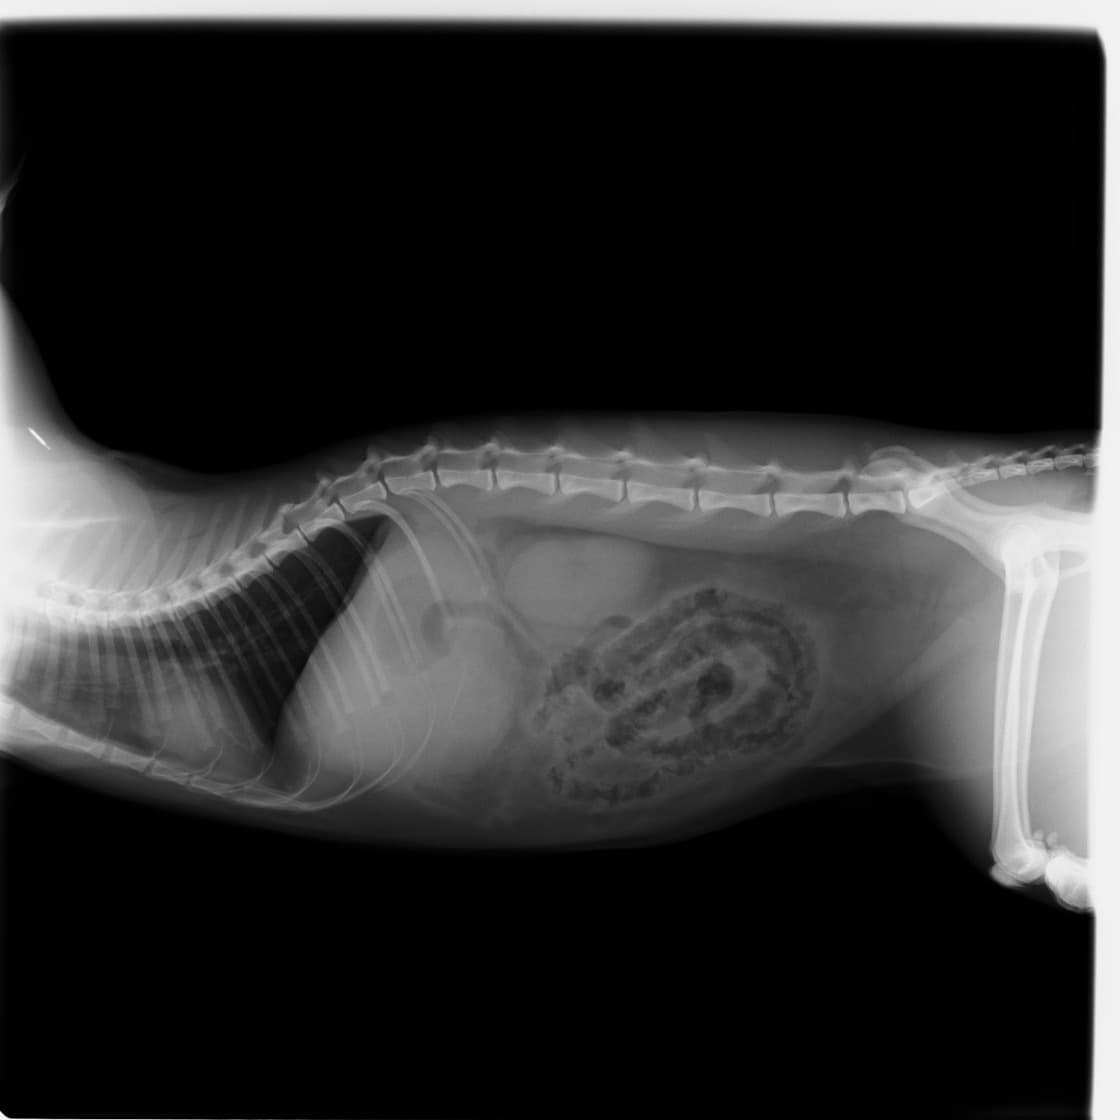

術前のレントゲン

身体検査上、鼓腸を伴う腹囲膨満、口腔粘膜の蒼白などが認められます。確定するには、レントゲン検査の実施が重要となります。その際、著しく拡張した胃が確認され、特徴的な捻転ラインが認められます。